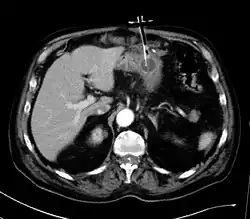

Die Anlage einer PEG wird im Rahmen einer Gastroskopie durchgeführt. Am häufigsten geschieht dies mit der sogenannten Fadendurchzugsmethode. Zunächst wird beim Patienten der Magen durch Einblasen von Luft entfaltet. Mittels Diaphanoskopie wird im abgedunkelten Raum eine günstige Position für die Sonde gesucht. Nach dem Anbringen einer örtlichen Betäubung und entsprechender Desinfektion wird ein wenige Millimeter langer Schnitt in die Bauchhaut durchgeführt. Durch diesen Schnitt wird eine Stahlkanüle bis in den Magen eingeführt. Über die Stahlkanüle ist ein Plastikröhrchen gestreift, das beim Zurückziehen der Stahlkanüle eine Verbindung durch die Haut in den Magen herstellt. Durch dieses Röhrchen wird jetzt ein Faden geschoben, der im Magen mit einer kleinen, durch das Endoskop geschobenen Zange gegriffen wird. Das Endoskop wird jetzt zurückgezogen, bis der Faden durch die Bauchwand, den Magen und die Speiseröhre führt und aus dem Mund des Patienten ragt. An dieses Ende wird nun die Sonde geknotet und schließlich durch Zug an dem aus dem Bauch ragenden Fadenende durch den Mund, die Speiseröhre und den Magen nach außen gezogen. Am inneren Ende der Sonde ist eine Plastikplatte (innere Halteplatte) befestigt, die ein Durchrutschen der Sonde nach außen verhindert. Von außen wird die Sonde durch eine Gegenplatte, auch äußere Halteplatte genannt, fixiert. Die Gegenplatte sollte über Nacht auf leichtem Zug, jedoch für die ersten drei Tage nach der Sondenanlage auf relativ festen Zug halten, damit die durchstochenen Schichten der Bauchwand und des Magens zusammenwachsen und sich ein dichter Kanal bildet.